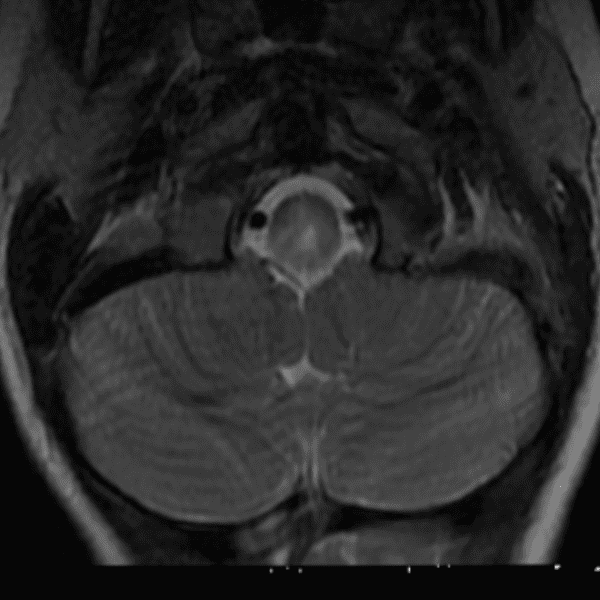

Simulates call by including subtle or difficult cases and some normals.

35 cases